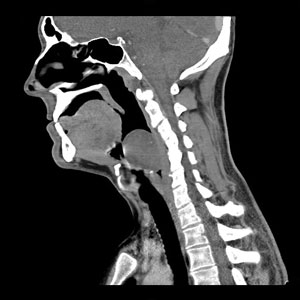

Flexible endoscopy examination revealed a well circumscribed, encapsulated tumour arising from the left lower lateral wall of the oropharynx and hypopharynx, and from the left arytenoid on its posterior aspect (Box 1). Computed tomography (CT) scanning revealed a 3 × 4.1 cm soft tissue mass arising from the left pharyngeal wall just inferior to the tonsillar fossa (Box 2).